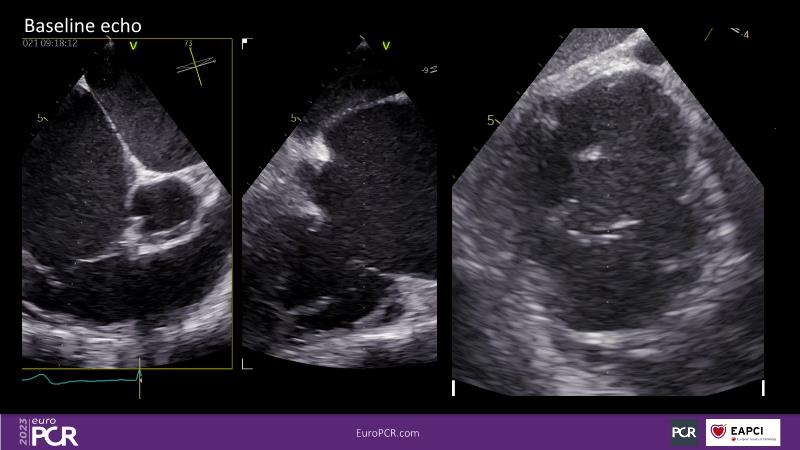

Tailoring tricuspid regurgitation patient treatment with the PASCAL Precision system

- To discuss the different tricuspid regurgitation phenotypes that can be treated with the PASCAL Precision repair system

- To participate in a case-based discussion using the PASCAL Precision repair system for the treatment of tricuspid regurgitation